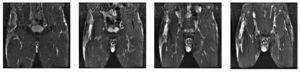

El 15 de noviembre de 2006 inició un cuadro de molestias en la región deltoidea derecha, sin antecedente traumático, con dolor a la palpación, enrojecimiento y calor local. Se encontraba afebril y no presentaba malestar general. Se realizó ecografía, en la que se observa colección anecoica extensa de 5 × 10 cm en el músculo deltoides derecho compatible con absceso muscular (fig. 1).

Figura 1 Imagen anecoica de bordes bien delimitados compatible con absceso muscular en deltoides.